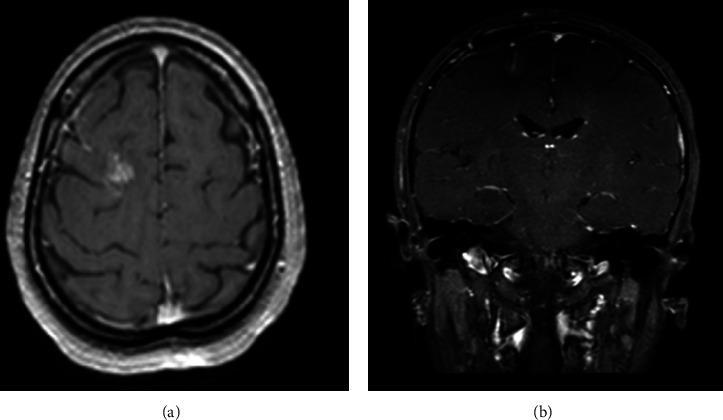

Schistosomiasis is a parasitic infection caused by schistosome invasion of blood circulation. Neuroschistosomiasis is a severe cerebral complication that accounts for less than 2.3% of reported cases. Patients present with progressive encephalitis, seizures, or both. Management includes antiparasitic medications, steroids, and surgical intervention. . We report a case of a 44-year-old female who presented to the ER with a history of transient loss of consciousness (LOC) and seizure. Radiological investigations revealed a right frontal brain lesion. Histopathological results confirmed the diagnosis of schistosomiasis.

血吸虫病是由血吸虫侵入血液循环引起的寄生虫感染。神经血吸虫病是一种严重的脑部并发症,在报告病例中占比不到2.3%。患者表现为进行性脑炎、癫痫发作或两者皆有。治疗包括抗寄生虫药物、类固醇和手术干预。我们报告一例44岁女性病例,该患者因短暂意识丧失(LOC)和癫痫发作史就诊于急诊室。影像学检查发现右侧额叶脑部病变。组织病理学结果确诊为血吸虫病。